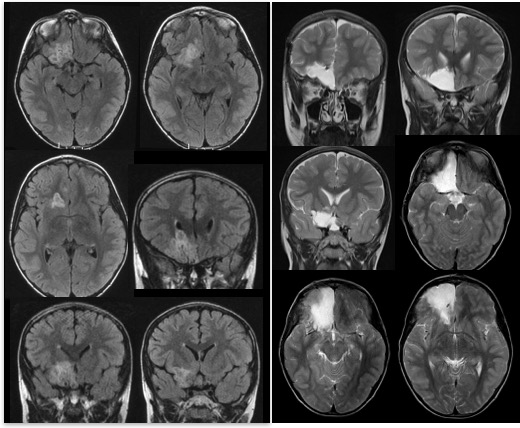

il peut s’agir de dysplasies corticales ou de tumeurs de bas grade. ces dernières sont en général peu ou pas évolutive, et souvent le diagnostic n’est fait que sur la pièce opératoire.

au total, ce sont généralement des lésions neuronales : tumorales ou dysplasiques.